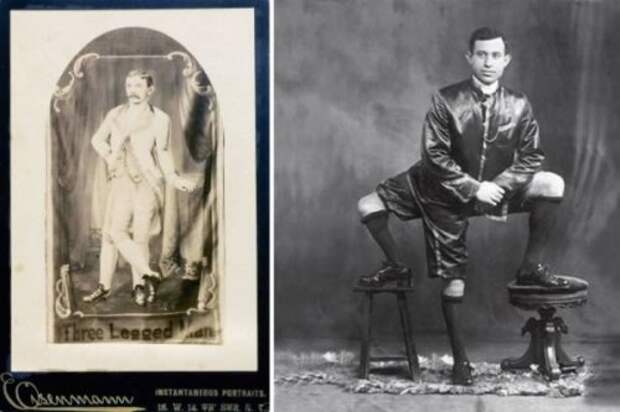

1. Женщина, которая родилась с двумя влагалищами

Хэйзел Джонс (Hazel Jones) всегда задавалась вопросом, почему она страдала от ужасных болей и обильных менструаций в период полового созревания.

Тем не менее, всё разъяснилось, когда ей исполнилось 18 лет и ей поставили поразительный диагноз, у неё два влагалища.

Светловолосая 27-летняя женщина из Хай-Уиком (High Wycombe) страдает от состояния, известного как uterus didelphys, которое встречается у одной женщины из миллиона и которое означает, что у неё есть две отдельные матки и шейки матки.

Хэйзел обратилась к врачу после того как её парень с которым она встречалась долгое время, сказал ей, что её половые органы «не такие как у других». Хэйзел говорит, что её не беспокоит её состояние, несмотря на то, что ей, по сути, пришлось терять девственность дважды.